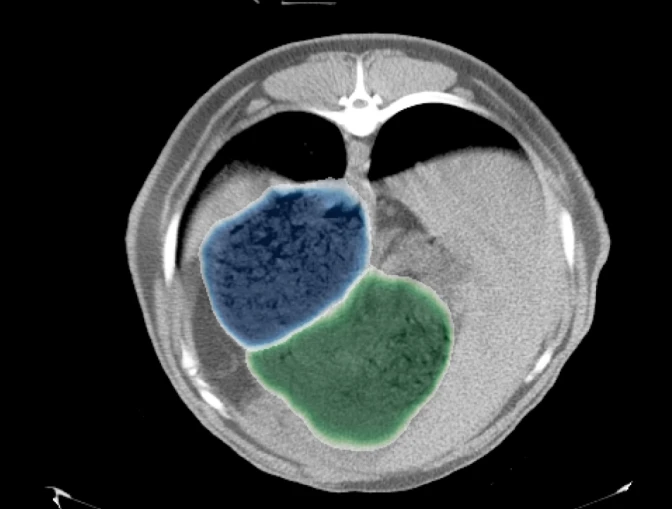

Predicted rumen blue and reticulum green areas of an independent test image

3D reconstruction of rumen and reticulum using predicted segments of a test animal